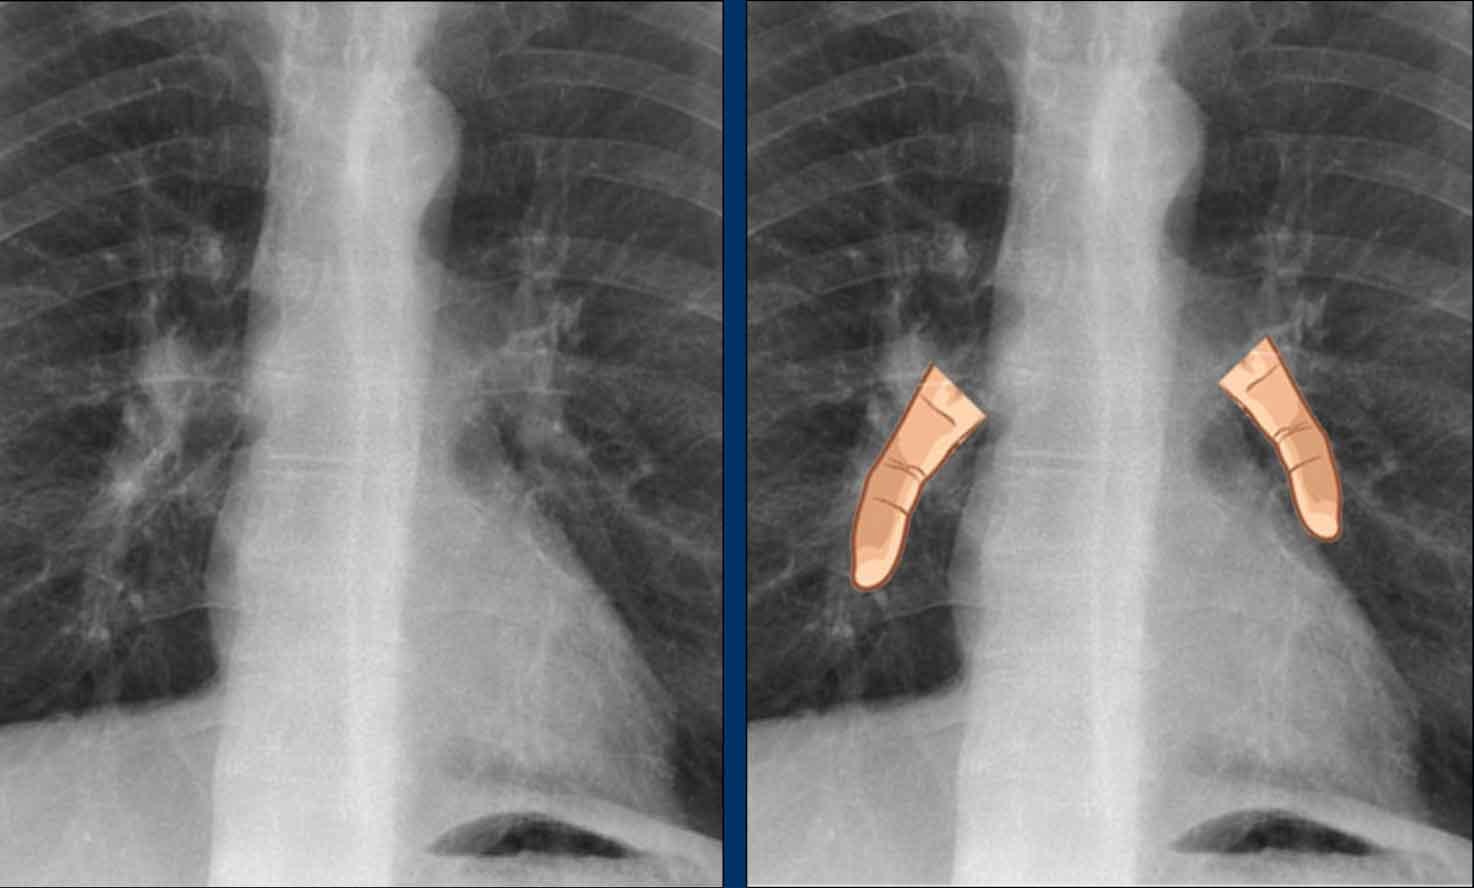

Thùy tĩnh mạch đơn

Một biến thể bình thường thường gặp, thùy tĩnh mạch đơn, được hình thành khi tĩnh mạch đơn đi theo một đường bất thường về phía bên, tạo ra một rãnh màng phổi sâu ở thùy trên phổi phải.

Trên phim X-quang, hình ảnh này biểu hiện là một đường cong mảnh đi ngang qua vùng phổi trên phải, thường kết thúc bằng một đám mờ hình giọt nước (tĩnh mạch đơn) trong rãnh tĩnh mạch đơn.

Đây là một bệnh nhân khác có thùy tĩnh mạch đơn.

Tĩnh mạch đơn được thấy như một cấu trúc dày trong rãnh tĩnh mạch đơn.